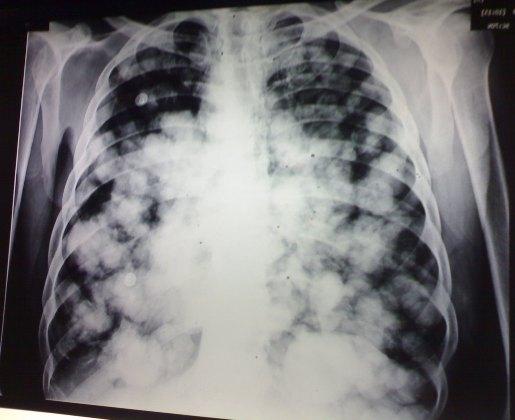

Fluffy-cotton appearance pneumonia